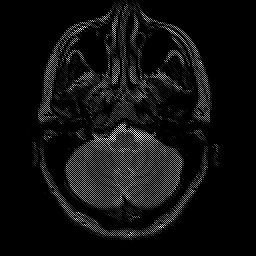

Glioma overlay -- Slice #5

[Home][Help][Clinical] Slice 5